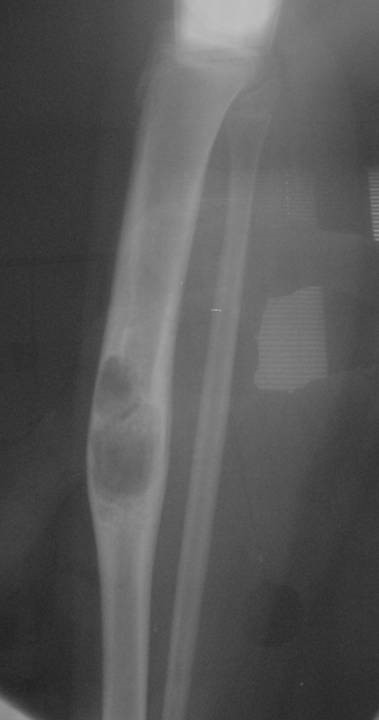

Radiographic Presentation

- Sharply defined osteolytic defect (lobulated, multicystic, or “soap bubble”)

- May be considerable perilesional sclerosis

Gross Pathology

- Sharp demarcation and lobulated configuration may be seen

- Solid areas are soft to firm, gray or white, granular or fibrous

- Cystic spaces and areas of intralesional hemorrhage are common

- Length: 5 cm to entire shaft